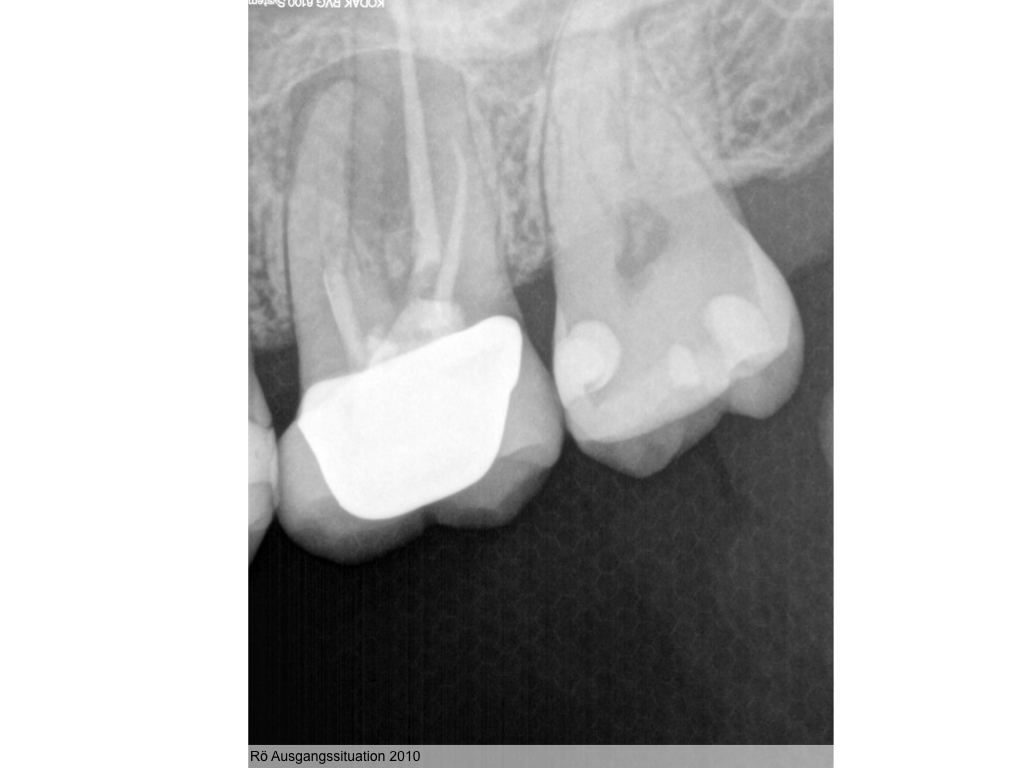

Heilung oder was?